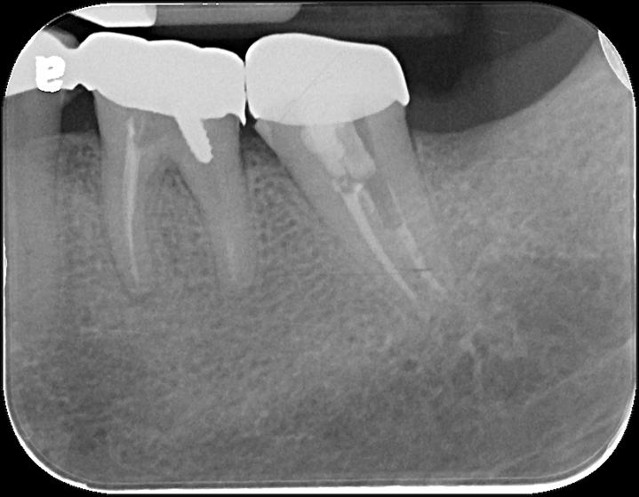

治療前,左下第二大臼齒蛀牙

治療前,左下第二大臼齒根管鈣化

顯微根管治療